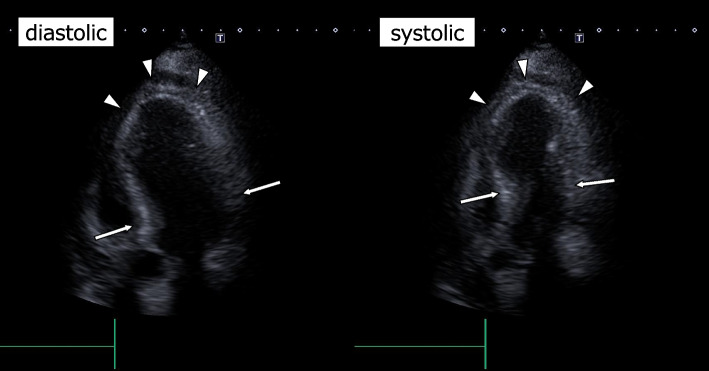

Case presentation: A 74-year-old woman received open hepatectomy for a hepatic tumor. During adrenal electrocauterization, abnormal hypertension and tachycardia suddenly occurred. Although the blood pressure returned to the baseline in a few minutes by nicardipine and landiolol, postoperative echocardiography revealed apical hypokinesis and basal hyperkinesis of the left ventricular wall with a decreased ejection fraction of 50%. Along with no coronary artery stenosis by CT angiography, a diagnosis of Takotsubo syndrome was made. Postoperative course was uneventful; ejection fraction increased to 69% with no obvious left ventricular wall asynergy at 1-month postoperative follow-up.